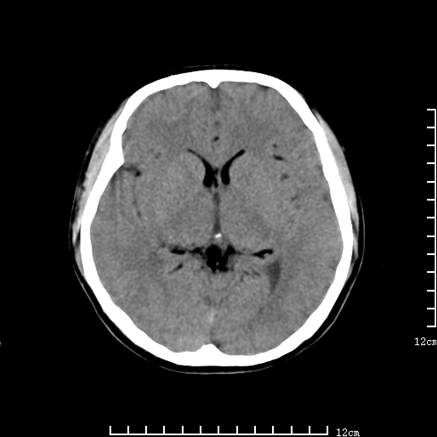

以下是引用jiajie在2008-9-5 22:25:00的发言:[br]男,22岁,头痛1月余。脑室、脑池内病变ct值约-120hu。[br][br]双侧侧脑室内低密度影充填,出现脑脊液脂肪平面,脑池内亦可见弥散分布的斑点状低密度影,脑室脑池未见明显扩大。[br]考虑胆脂瘤破裂后内容物进入脑脊液。